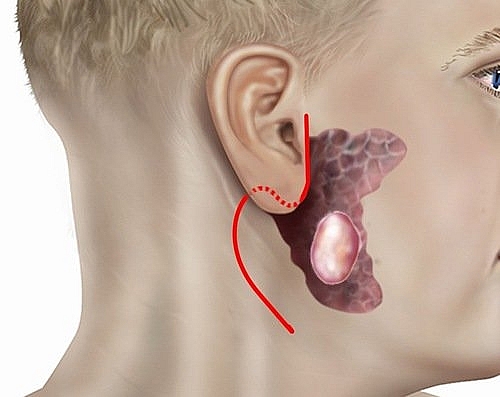

Dấu hiệu nhận biết ung thư tuyến nước bọt

Ung thư tuyến nước bọt là gì? Dấu hiệu nhận biết ung thư tuyến nước bọt và những điều cần biết sẽ có trong bài viết này: